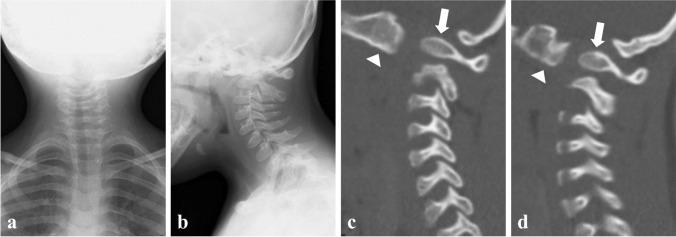

Down syndrome, also known as trisomy 21, is associated with congenital cervical spine abnormalities, including atlantoaxial instability with or without os odontoideum, atlanto-occipital instability, and hypoplasia of the atlas. Herein, we report a case of Down syndrome complicated by congenital atlanto-occipital dislocation. The patient presented with severe cervical myelopathy at 13 years of age after a 10-year follow-up. Radiography and computed tomography revealed os odontoideum protruding into the foramen magnum and congenital anterior atlanto-occipital dislocation. Additionally, a bifurcated internal occipital crest with a thinned central portion of the occipital bone was noted. Magnetic resonance imaging revealed kyphotic alignment of the spinal cord with severe compression at the foramen magnum level. As the neurological impairment was partially improved by halo vest immobilization, we performed in situ O-C2 fusion with an iliac autograft and decompression of the foramen magnum and posterior arch of C1. An improvement was observed immediately after surgery. Two years after surgery, radiography and computed tomography showed solid O-C2 segment fusion. The accumulation of similar cases is essential for determining the prognosis or optimal treatment for this rare congenital condition.

唐氏综合征,又称 21 三体综合征,与先天性颈椎异常相关,包括寰枢椎不稳伴或不伴齿状突游离、寰枕不稳和寰椎发育不良。本文报告一例唐氏综合征并发先天性寰枕脱位。患者 13 岁时,经过 10 年随访,出现严重的颈髓病变。影像学检查显示齿状突突入颅后窝,先天性寰枕前脱位。此外,还可见分叉的枕内嵴,伴有枕骨中部变薄。磁共振成像显示颈椎呈后凸排列,在颅后窝水平严重受压。由于 halo 背心固定术使神经功能缺损部分改善,我们进行了原位寰枢椎融合术,取自体髂骨,并进行颅后窝和 C1 后弓减压。术后即刻观察到改善。术后 2 年,影像学检查显示寰枢椎融合稳定。此类病例的积累对于确定这种罕见先天性疾病的预后或最佳治疗方法至关重要。